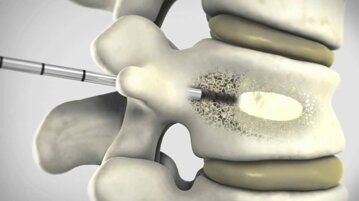

La vertebroplastica e la cifoplastica sono procedure mini-invasive utilizzate per trattare fratture vertebrali dolorose, spesso causate da osteoporosi o traumi. Entrambe consistono nell’iniezione di cemento osseo all’interno della vertebra fratturata, ma la cifoplastica prevede anche l’utilizzo di un piccolo palloncino per riallineare la vertebra e recuperare parte della sua altezza originaria.

La procedura si esegue in anestesia locale o generale, con guida radiologica. Nella vertebroplastica si inserisce un ago nella vertebra e si inietta cemento osseo per stabilizzarla. Nella cifoplastica, prima di iniettare il cemento, si introduce un piccolo palloncino che viene gonfiato per rialzare la vertebra collassata. La durata è di circa 30-60 minuti.